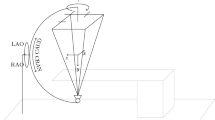

Printing the integrated 3D coronary model with a flat base

To eliminate the influence of heartbeat and respiration and inconsistencies of body position during CT and CAG, a coronary artery model developed from 3D CT reconstruction was obtained from Shanghai Preclinic Medical Technology (China). In this procedure, a digital flat base for the coronary artery digital model was fused using UG NX software (version 11.0) before printing, and then integrally printed using 3D technology (Fig. 2A). Compared with the post-assembly of the coronary model and the flat base, integrated printing can prevent shifts between the coronary model and the flat base (which can easily occur during post-assembly) and thus ensure that the actual position of the printed coronary artery model and the flat base were consistent with the engineered version.

Effects of common DSA gantry movements on the DSA image. Note the image position on each screen. A, 3D printed coronary model. B, Lowering the detector. C, Lowering the platform. D, Moving the image to the upper edge of the screen without changing the gantry angle. E, Moving the image to the right edge of the screen. F, Rotating to the CRA view with the model lower than the isocenter. G, Rotating to the LAO view with the model lower than the isocenter. H, Rotating to the LAO or CRA view with the model at the isocenter. LAO: left anterior oblique; CAU: caudal; CRA: cranial

The coronary model was placed on the DSA platform. Then, several common DSA gantry movements (changing the height of the platform and detector, shifting the platform horizontally, and changing the gantry angle) were performed during the PCI procedure to identify factors that affect DSA image transformation.

Effects of common DSA gantry movements on the DSA image

We found that raising or lowering the DSA detector caused no changes in the DSA image (Fig. 2B), but lowering or raising the platform led to obvious changes (Fig. 2C and Suppl. Video 1). Furthermore, when the DSA image deviated from the previous position of the screen due to horizontal shift of the platform, it rotated automatically without changing the gantry angle (Fig. 2D and E, and Suppl. Video 2). When the coronary artery model was at the DSA isocenter (the intersection of the C-arm rotation axis and the Pivot-arm), the DSA image maintained its position on the screen regardless of gantry angle (Fig. 2H). For a stationary platform, when the model was lower or higher than the isocenter, the DSA image deviated from the previous position of the screen after gantry rotation. Due to the changing position of this image, it was not identical to the image from the previous position after rotation. However, we eliminated this inconsistency by shifting the platform horizontally, so that the DSA image returned to the previous position (Fig. 2F and G, and Suppl. Video 3). These findings indicated that DSA image transformation is completely determined by DSA gantry angle, the distance of the X-ray tube to the platform, and the position of the DSA image on the screen.